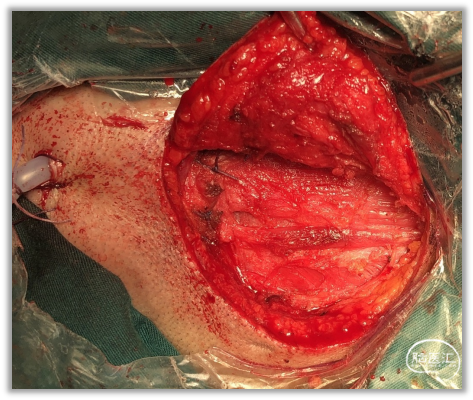

▼15.小脑绒球下入路

小脑绒球下入路(infrafloccular approach)最早由日本专家Matsushima提出。因为绒球和从Luschka孔突出的脉络丛从外侧遮挡面神经REZ区(下图),而且,在绒球和前庭蜗神经之间经常有黏连,还可能存在大量坚韧的蛛网膜小梁,因此从小脑外侧间隙很难暴露REZ区,还可能造成听力损伤。

绒球下入路(上图)就是抬起小脑的下外侧缘,打开舌咽神经和迷走神经后方的蛛网膜,便可暴露由Luschka孔突出的位于舌咽神经和迷走神经后面的脉络丛,将脉络丛从舌咽神经后缘轻轻分开,以暴露舌咽神经与脑干连接处。脑板进一步向上将脉络丛从舌咽神经后缘上抬起,暴露范围向舌咽神经上方扩展数毫米,此处即为面神经与脑干的连接处(REZ区),恰位于前庭蜗神经的前下方。

▼17.锐性地分离后组颅神经的蛛网膜,并辨认出舌咽神经。

充分松解后组颅神经背侧蛛网膜,若松解不充分,就无法获得从下向上的视野。

充分松解的标准就是能看清后组颅神经出入延髓橄榄后沟的神经根丝。

充分释放脑脊液后,此后的操作可不用脑压板,采用吸引器来动态地牵开小脑,动态牵拉既会减少听力受损的概率,也会充分暴露术中所需要的解剖区域。

钝性分离(用圆头显微剥离子)和锐性分离(用显微剪刀)结合将责任血管充分游离后,向颅底方向推移离开面神经出脑干区。注意勿损伤动脉向脑干发出的穿动脉及走向内听道的内听动脉,并避免器械触及面、听神经。

可以采用聚四氟乙烯(Teflon)单点支撑(下图)、桥型支撑、棉条悬吊、胶水黏附悬吊等。责任血管(一般是小脑前下或后下动脉)就在面神经的腋部,抬起血管,将血管与神经分离后即可垫入Teflon。

减压垫棉置于责任血管与脑干之间,必要时可用第2、第3 块垫棉进一步推开血管以求减压充分。有学者建议应避免将垫棉放置在责任血管与面神经出脑干区之间,亦不可与之接触以防局部发生粘连而致术后复发(桥型支撑)。另有学者建议责任血管与面神经REZ区域及脑干相邻全程均要用Teflon垫开(下图)。

Teflon是目前最常用的减压材料,Teflon棉(下图)显示出较Teflon片和Teflon球更好的减压效果,它既不容易对面神经根造成新的压迫,也不容易移位,且有助于粘连固定住责任血管。垫棉不宜过大以免形成新的压迫。置入垫棉后应确保其固定,防止滑脱。责任血管垫开后注意动脉不能扭曲成角。